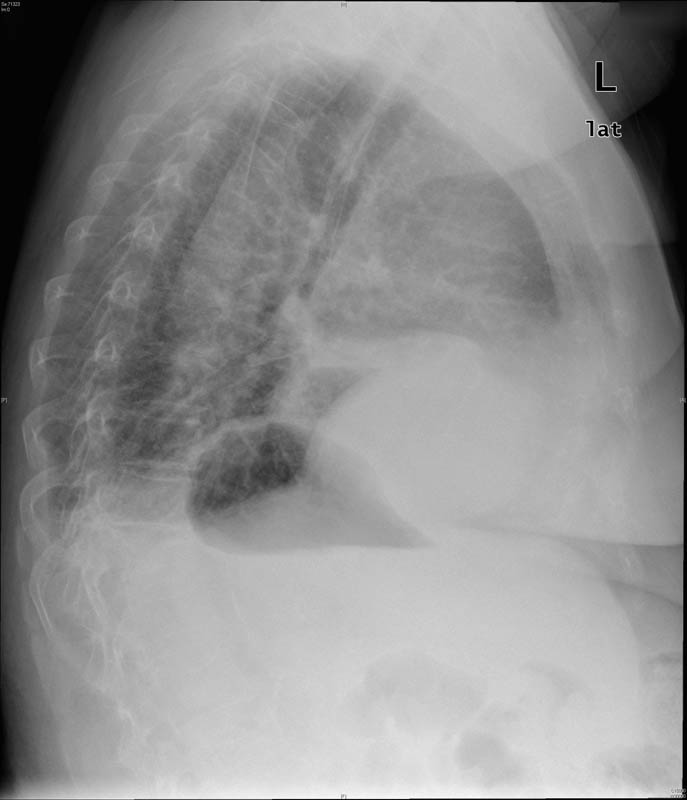

Tumoración mediastínica